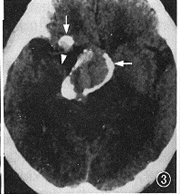

例2 男,38岁。复视,右眼视力下降半年。外院诊断颅咽管瘤,来本中心求治。体检:右外展神经麻痹,右眼视力0.8。CT平扫(图3):鞍旁4.0 cm×3.0 cm×5.0 cm高密度占位,右侧裂内1.0 cm×0.8 cm×1.0 cm高密度占位,边界清,周边呈蛋壳样钙化。MRI示鞍区、鞍上混杂信号占位,边界清,内有流空信号和不同强度短T1、长T2信号,周围脑组织受压水肿(图4,5)。MRA示右颈内动脉蛇形血管通道,累及右大脑中和大脑前动脉(图6)。DSA示右颈内动脉自岩段起呈蛇形迂曲扩张, 累及右M1、A1段及右后交通动脉,血管通道内血流缓慢,静脉窦期仍见对比剂滞留(图7,8)。右颈内动脉球囊闭塞加强试验阴性,但交叉代偿循环充盈试验阳性,先行右颞浅动脉-大脑中动脉搭桥术,术后24 h内,右颈外动脉造影显示吻合口通畅,遂行载瘤动脉近端球囊闭塞术,载瘤动脉闭塞后右颈外动脉造影显示通过吻合口的血流增加(图9)。术后1年随访,症状、体征消失,生活工作正常,CT复查:瘤周脑组织水肿消失,大小无明显变化。

图3 CT平扫,示右鞍旁、鞍上不均质高密度占位,大小3.0 cm × 5.0 cm × 4.0 cm ,周边弹壳样钙化(↑)。右侧裂内不均质占位(Δ),部分钙化,大小1.0 cm × 0.8 cm×1.0 cm ,周围脑组织受压移位